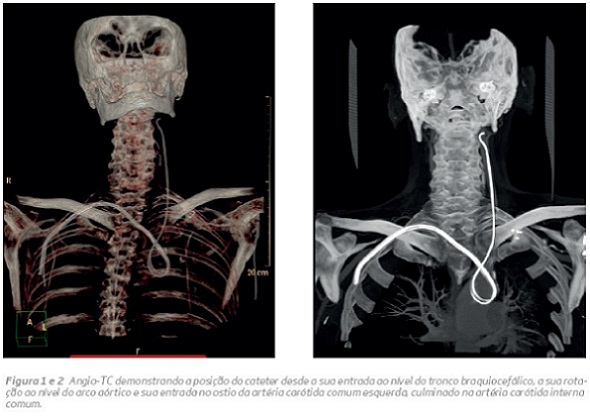

Doente do sexo masculino, 79 anos, hipertenso e com doença renal crónica (DRC) estadio IV, que encontrava internado por agudização da DRC, com necessidade de início de hemodiálise. Transferido após tentativa de colocação de cateter de hemodiálise na veia jugular interna direita, complicada de cateterização acidental da do tronco braquiocefálico (entre a artéria subclávia direita e artéria carótida comum direita, o que impossibilitava uma solução de tratamento endovascular) com progressão do cateter até à artéria carótida interna esquerda – como demonstrado por AngioTC (figura 1 e 2).